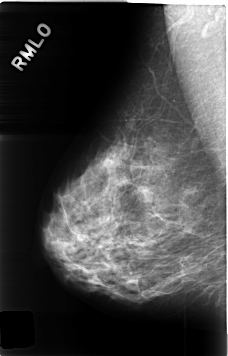

C_0468_1.RIGHT_MLO

RIGHT_CC LINES 4576 PIXELS_PER_LINE 2984 BITS_PER_PIXEL 12 RESOLUTION 50 NON_OVERLAY

RIGHT_MLO LINES 4624 PIXELS_PER_LINE 2952 BITS_PER_PIXEL 12 RESOLUTION 50 NON_OVERLAY